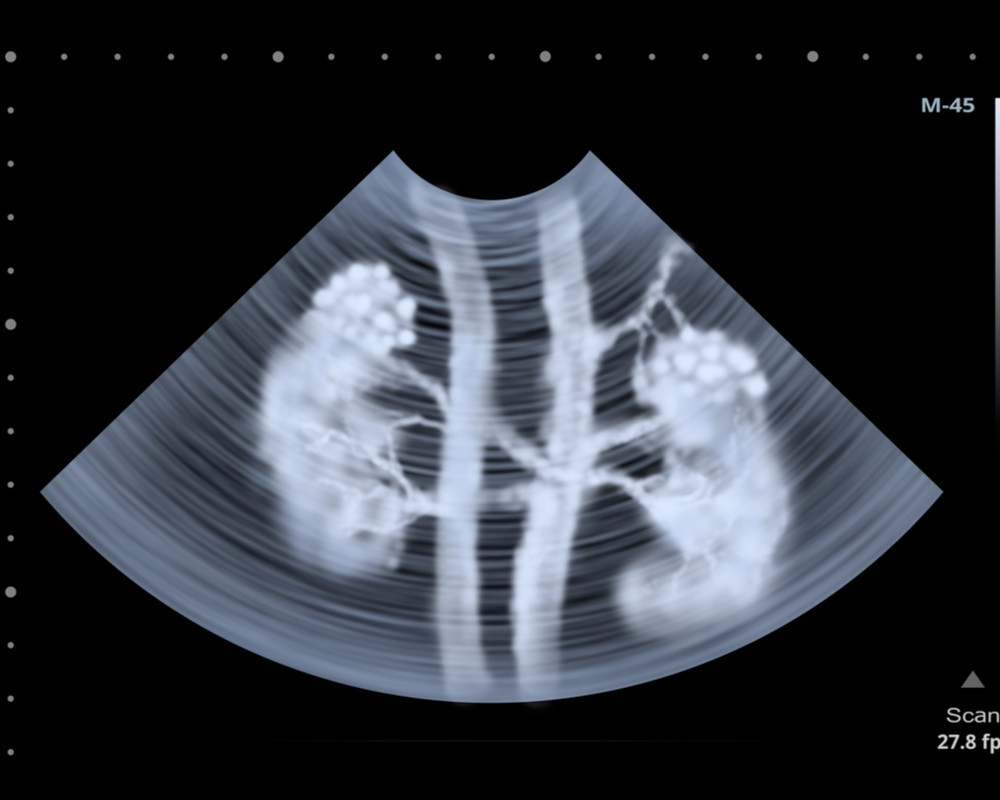

ЦДК сосудов почек: что это и как проводится